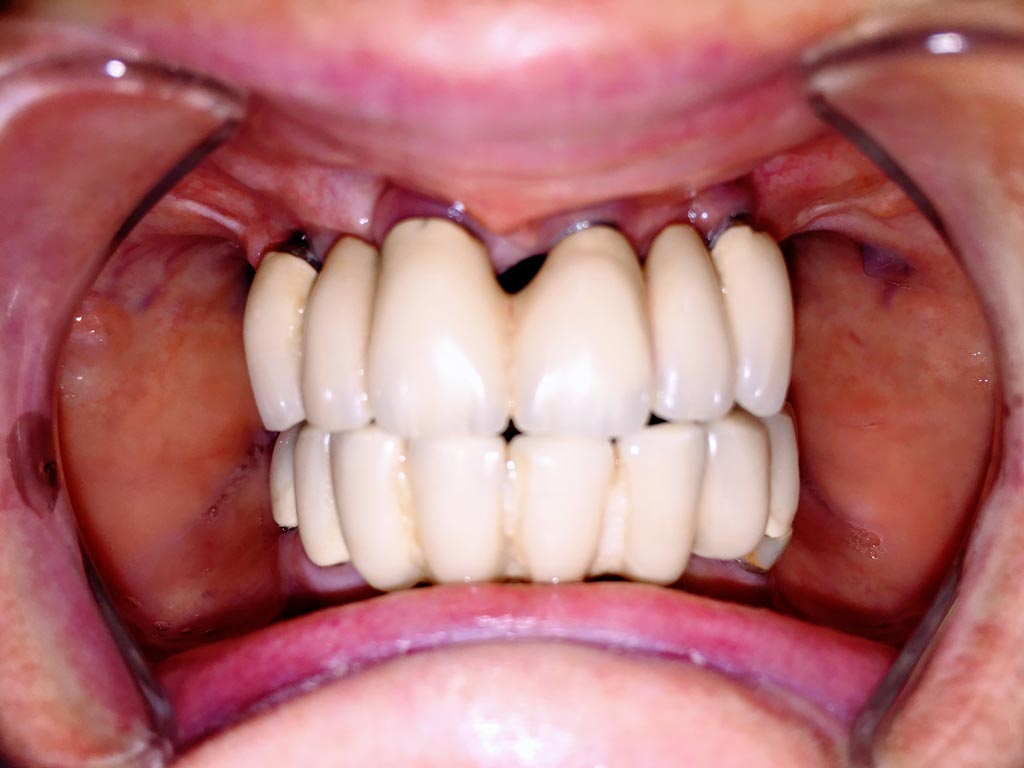

Teljes fogatlanság helyreállítása 2 nap alatt

Teljes fogatlanság helyreállítása 2 nap alatt azonnal terhelhető svájci IHDE implantátumokkal és PMMA műanyag hidakkal. Intraorális szkennerrel vettünk lenyomatot az implantáció után, és erre a digitális mintára készítette el a fogtechnika a hidak digitális tervezését, majd faragta ki műanyagból. Ezt a gyors munkát az azonnal terhelhető implantátumok és a digitális lenyomat, tervezés segítségével tudtuk megcsinálni mindössze 2 nap alatt. Dr. Kelemen Péter és a Symbion Fogtechnika munkája.